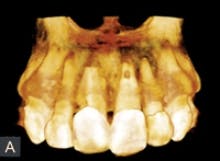

Fig. 3 — This 3-D rendered model is a representation of the bone loss and extent of the apical resorption in tooth No. 9. Note also the cervical root resorption of tooth No. 8.